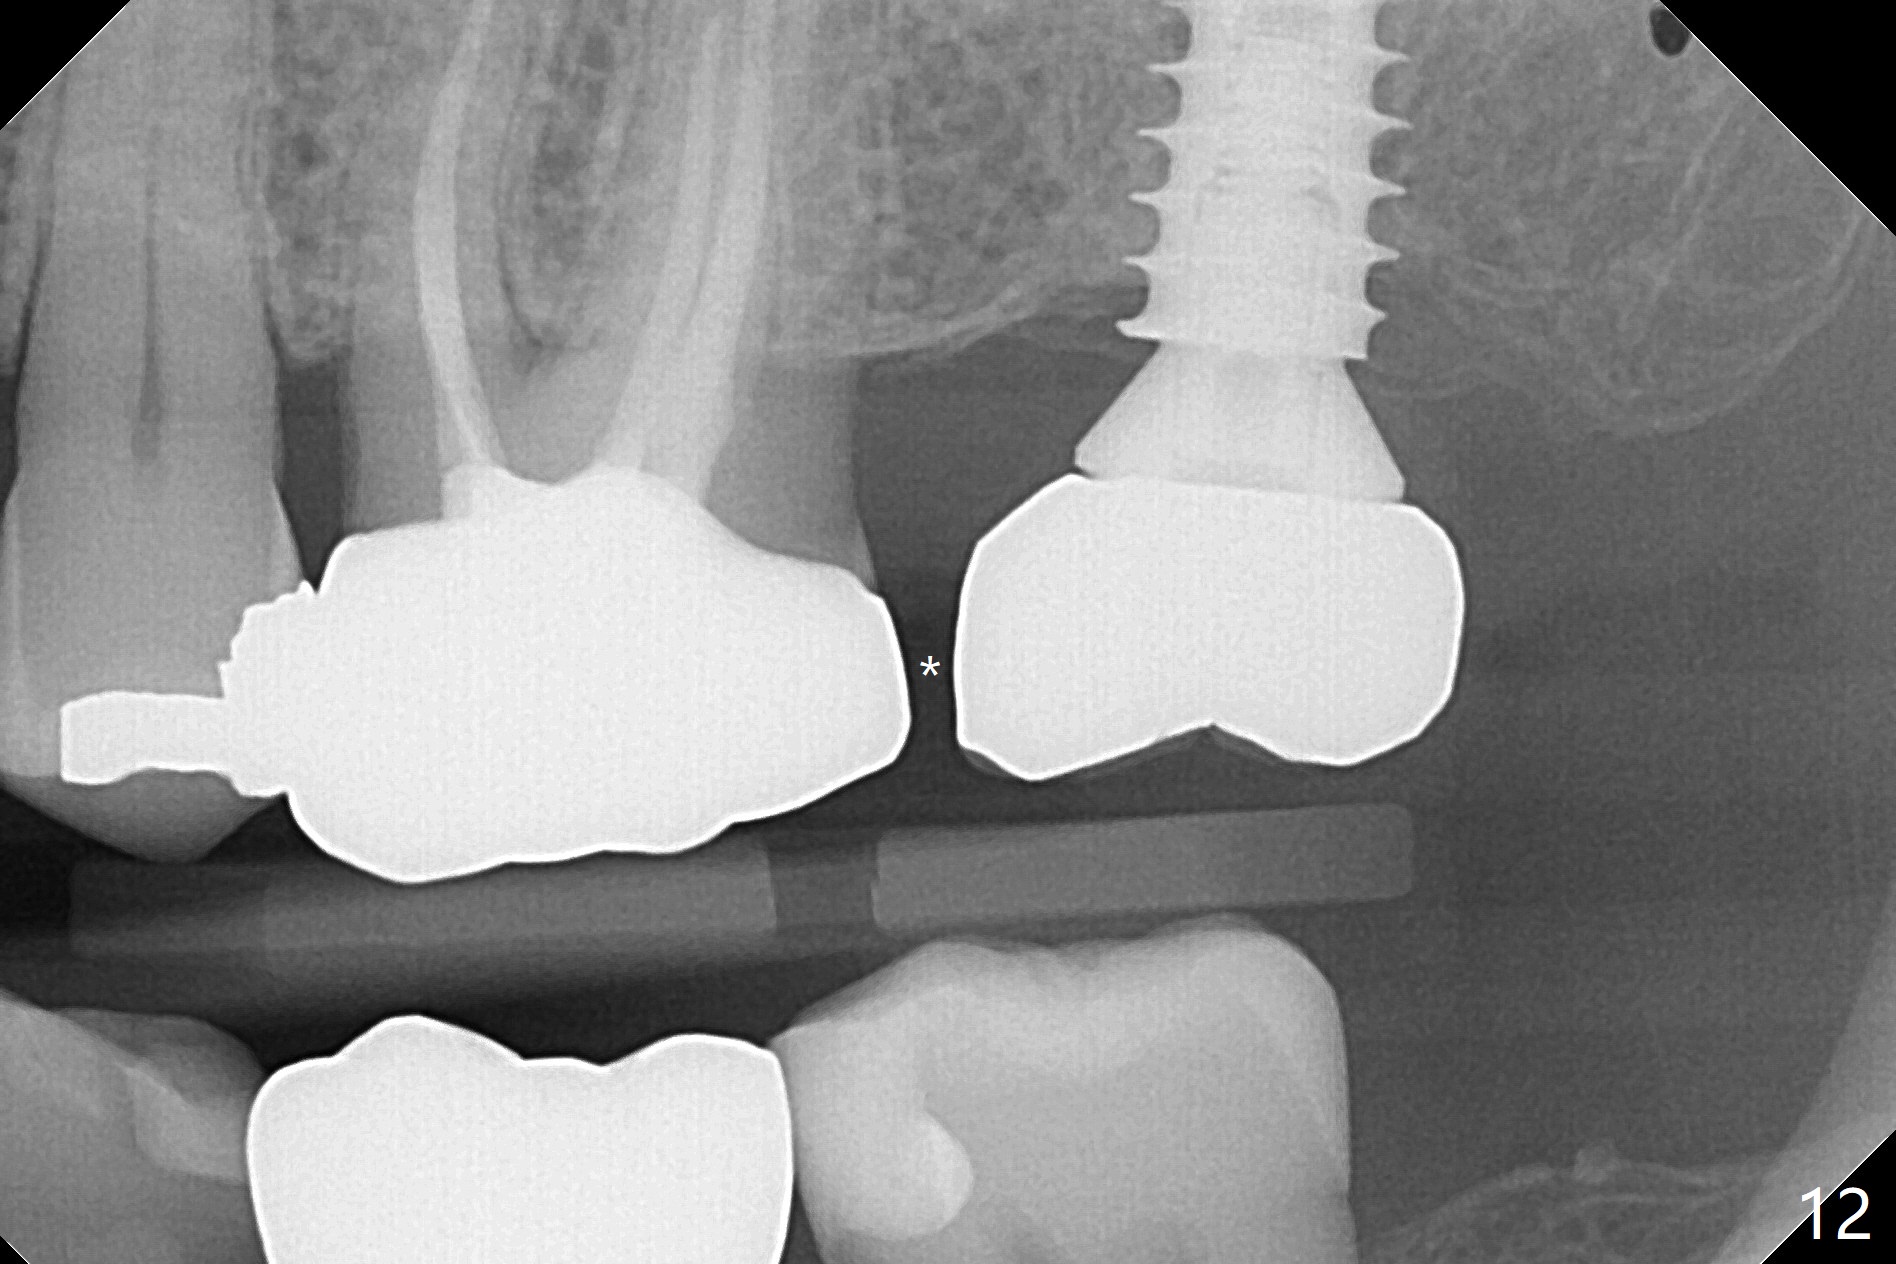

The ridge is pointed at the site of #15 (Fig.1). A 1.2 mm initial drill is used to start osteotomy for 10 mm, followed by an incision over the ridge mesiodistally for ~ 8 mm. After tapping the #15 C blade, the 1st Bone Expander 1.0/1.6 mm) is inserted for ~ 11 mm (Fig.2, 20 Ncm). Bone expansion continues until #4 Expander (2.4/3.7 mm, Fig.3). When 4x11 mm and 4.5x11 mm dummy implants are placed (Fig.4), insertion torque remains 20 Ncm. Following placing allograft with 3-4 amalgam carriers, a 5x11 mm IBS implant is placed with 20 Ncm (Fig.5,6). In fact the implant turns when an abutment is placed. When the implant is re-inserted, torque decreases to 10 Ncm. Instead a healing screw is placed. The low torque value is due to soft bone and failure to underprep. #4 Expander (Fig.3) seems larger than 4.5 mm implant (Fig.4). #3 Expander (1.7/3.1 mm) should have been used prior to definitive implant placement. The implant appears to have osteointegrated 3 months postop (Fig.7); impression is taken. The bone density at the crest increases 1.5 years post cementation (Fig.8 *, as compared to Fig.6), although there is mild bone loss. Implant placement should be deep when bone expansion is carried out. The tooth #14 develops a buccal fistula, corresponding to periapical radiolucency of the mesiobuccal root (Fig.9 white >). The abutment of #15 may be incompletely seated (black <). PA taken when RCT of #14 is finished does not show the incomplete seating of the abutment (Fig.10). Since there appears no history of abutment screw loosening, the abutment is not reseated when #14 is prepared for crown. Recall 3 years 7 months post cementation shows incomplete seating of the abutment (Fig.11 >). After crown proximal reduction (Fig.12 *) and clockwise turn of the crown, the abutment appears to be completely seated. When the case returns from lab, the separate crown and abutment cannot be connected to the fixture because of soft tissue adaptation and change in a month. The abutment is reseated to the fixture analog in the model and the crown is recemented with temp bond (in case of misalignment) while making sure that the crown has the best proximal contact with the neighboring crown. With the abutment and crown in a unit, it is much easier to reseat the abutment with normal proximal contact. The torque is 20 Ncm. The access hole is closed with Cavit.